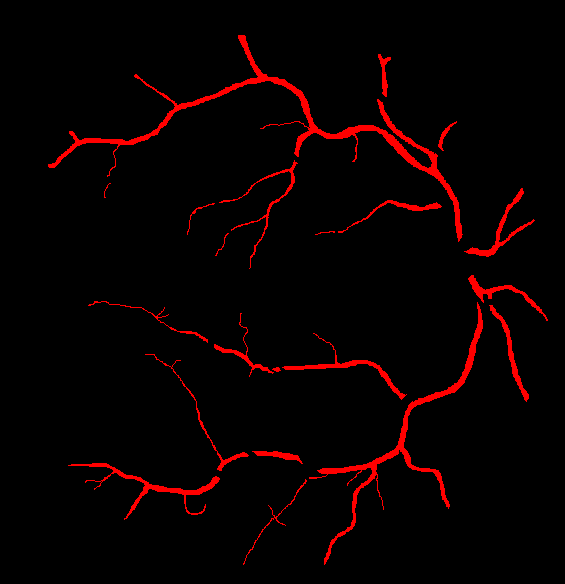

The visual differentiation between arteries and veins can be difficult in some cases, like small vessels with poor contrast and not clearly connected to a specific arterial or venular tree. These cases can be identified with certainty as vessels, but their classification into arteries and veins is uncertain, even for an expert. Additionally, it is common to find crossings between arteries and veins in the retina. Thus, although for these positions either the artery or the vein is above the other, these pixels can be regarded as simultaneously belonging to both types of vessels. This allows to account for continuous arterial and venular trees regardless of crossings below the other one. The identification of these two special situations (uncertain vessels, and vessel crossings) is common in manually annotated retinal vessel classification datasets [38, 42, 43, 44]. Figure 1 shows an example of a ground truth image from the RITE dataset labelled this way, along with its decomposition into arteries, veins, crossings and uncertain vessels.

Also, an example of a retinography and its corresponding vasculature segmentation and A/V classification ground truths is depicted in Figure 6.

In order to train the networks following the traditional and MS approaches, the ground truth images from the RITE dataset are adapted, in each case, to the output of the network. In the traditional approach, each pixel of the ground truth is assigned to either background, artery, vein or “uncertain or crossing” class, which comprises both uncertain vessels and crossings. The resulting ground truth is a grayscale image in which each pixel has a numeric label of the class to which it belongs. On the other hand, in the MS approach, each pixel is assigned to any number of the following classes: artery, vein and vessel. In this case, crossings belong to the three classes, and uncertain vessels belong only to the “vessel” class. Background pixels are not assigned to any class. The resulting ground truth is an RGB image in which each channel contains a manual segmentation mask of one of the aforementioned structures. An example of a RITE ground truth adapted to both the traditional and the MS approaches can be found in Figure 7.